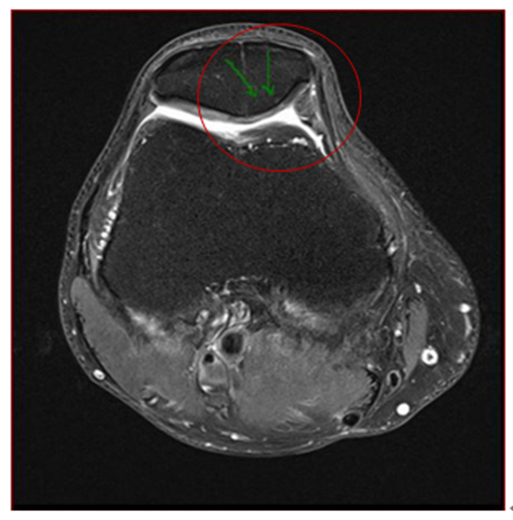

MSCs治疗后33个月,患者的MRI表现仍然稳定,显示髌骨骨髓水肿和囊肿完全消退(图3),内侧半月板撕裂状态稳定,软骨损伤没有进一步发展。

图3:间充质干细胞治疗后33个月显示髌骨骨髓水肿和囊肿完全消退。

图片来源:【1】